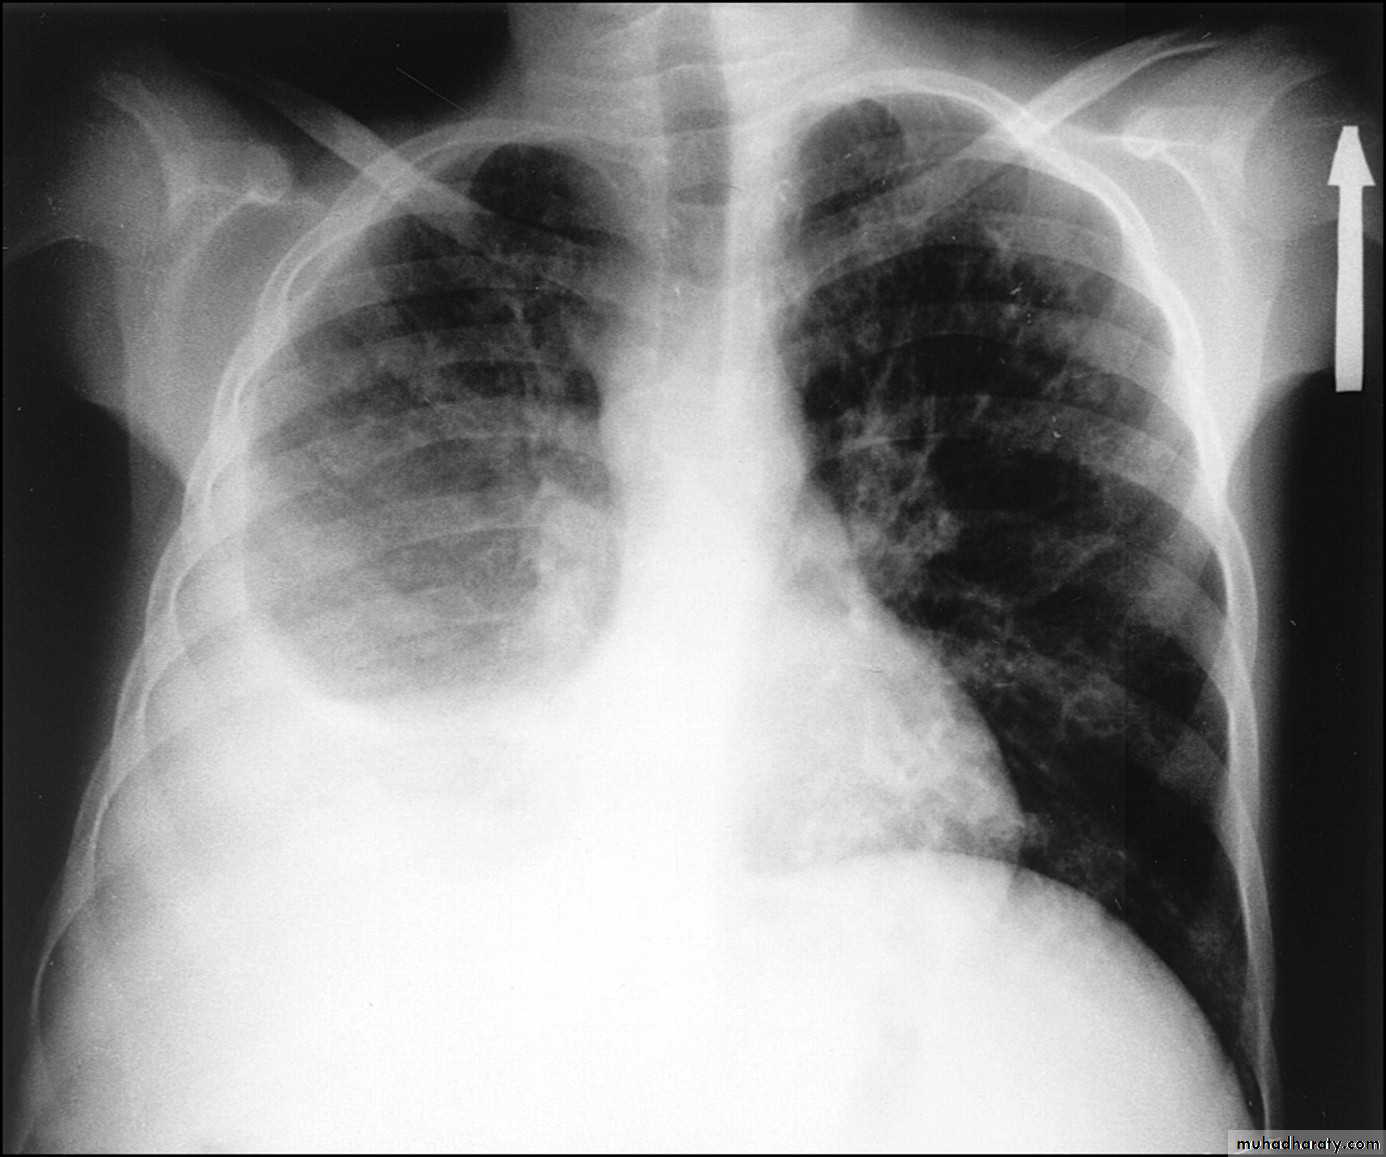

Bronchiectasis

59.Bronchiactasis